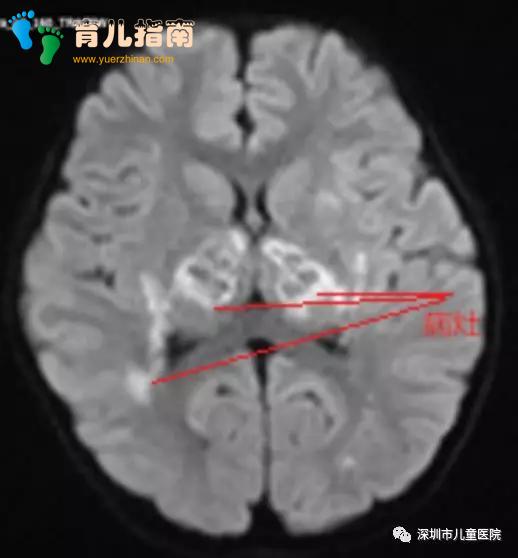

发烧第四天,核磁共振检查传来坏消息:她的脑部多发病灶,典型的急性坏死性脑病!PICU医生团队仔细分析后认为,这很可能是流感引起的脑病。进一步的检验后,祸首”被揪了出来——甲型流感。

通过检查发现这孩子的头颅CT是一个明显的多发病灶,我们考虑孩子是一个甲流病毒引起的急性坏死性脑病。急性坏死性脑病是儿童在甲流里经常会碰到的并发症,孩子很快会出现意识障碍,严重的甚至会出现脑损伤。